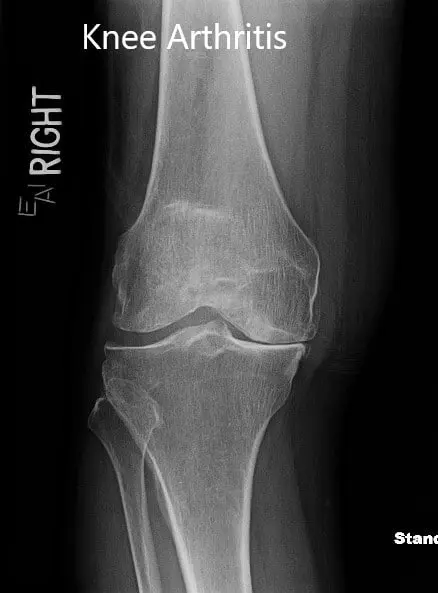

The imaging results revealed severe tricompartmental osteoarthritis of the knee. Considering his lifestyle limiting knee pain, he was advised right total knee replacement with custom instruments. The risks, benefits, and alternatives were discussed with the patient at length. He agreed with the plan.

Preoperative X-ray showing the anteroposterior and lateral view of the right knee.